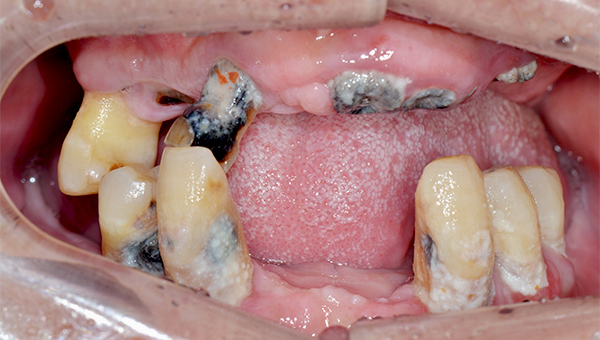

박*수 임플란트 시술 사례

전체 임플란트

20**.**.**

치료 전

치료 후